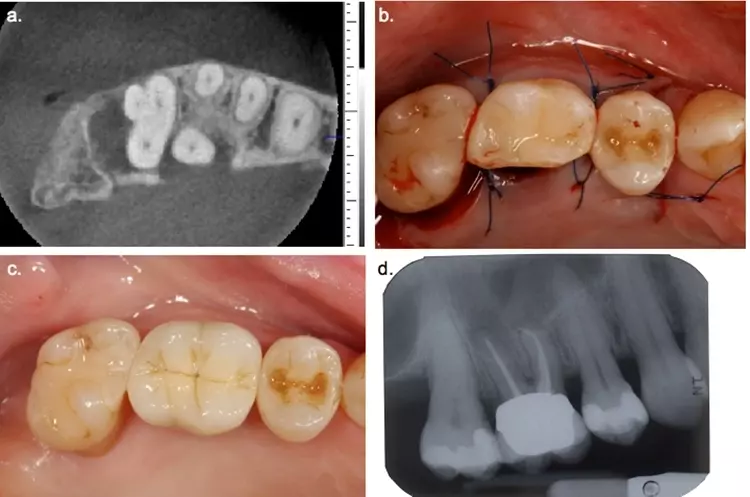

Aufgrund mehrerer lokalisierter, vertikaler Einbrüche im 2. (Zahn 22 und 25) und 3. Quadranten (Zahn 35) wurden jetzt regenerative parodontalchirurgische Operationen mit Schmelz-Matrix-Proteinen (Zahn 25) und synthetischem Knochenersatzmaterial (Emdogain Plus, Zähne 22 und 35) durchgeführt. Es konnten lokalisierte dreiwandige Knochendefekte dargestellt werden. Die gewählte Schnittführung im Sinne eines Papillenerhaltungslappens ermöglichte einen dichten Wundverschluss und strebte den Erhalt der roten Ästhetik an (Abb. 10 und 11).

Dr. Mauro Amato & Prof. Clemens Walter